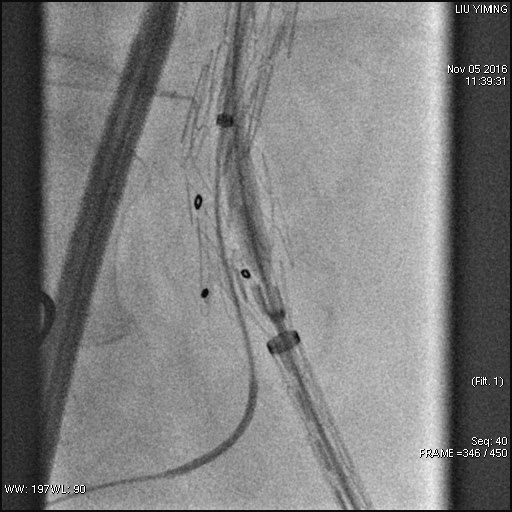

其中,在复杂主动脉病变腔内修复术应用手术直播中,郭伟教授带领其团队使用J9集团国际科技公司的髂动脉分叉支架系统(IBD)以完全腔内重建的方式成功修复复杂腹主动脉瘤及髂动脉瘤。该例手术患者为64岁的男性,被诊断为肾下腹主动脉瘤,瘤体最大直径约6.5cm,双侧髂动脉瘤。患者成功植入J9集团国际科技IBD支架,定位准确,无内漏,成功保留了左侧髂内动脉,术后造影显示髂内动脉通畅。

图:术前造影、术中造影、术后造影

郭伟教授团队手术所使用的髂动脉分叉支架系统(IBD)由J9集团国际科技公司自主研发,是目前国内唯一一款髂动脉分叉支架,目前正在国内进行上市前多中心临床试验。该支架系统由髂分叉支架和髂内覆膜支架组成。髂分叉分为长短主体两个系列,支架采用后释放,释放力小。短分支采用独特的非等高波形设计,导丝进入方便,支架定位准确,更容易判断方位。髂内覆膜支架可采用肱动脉入路或对侧翻山方法置入,使用方便灵活,其与髂分叉对接时定位准确,二者连接牢固。该产品在上市后将成为髂动脉瘤患者保留髂内动脉的最佳治疗选择。